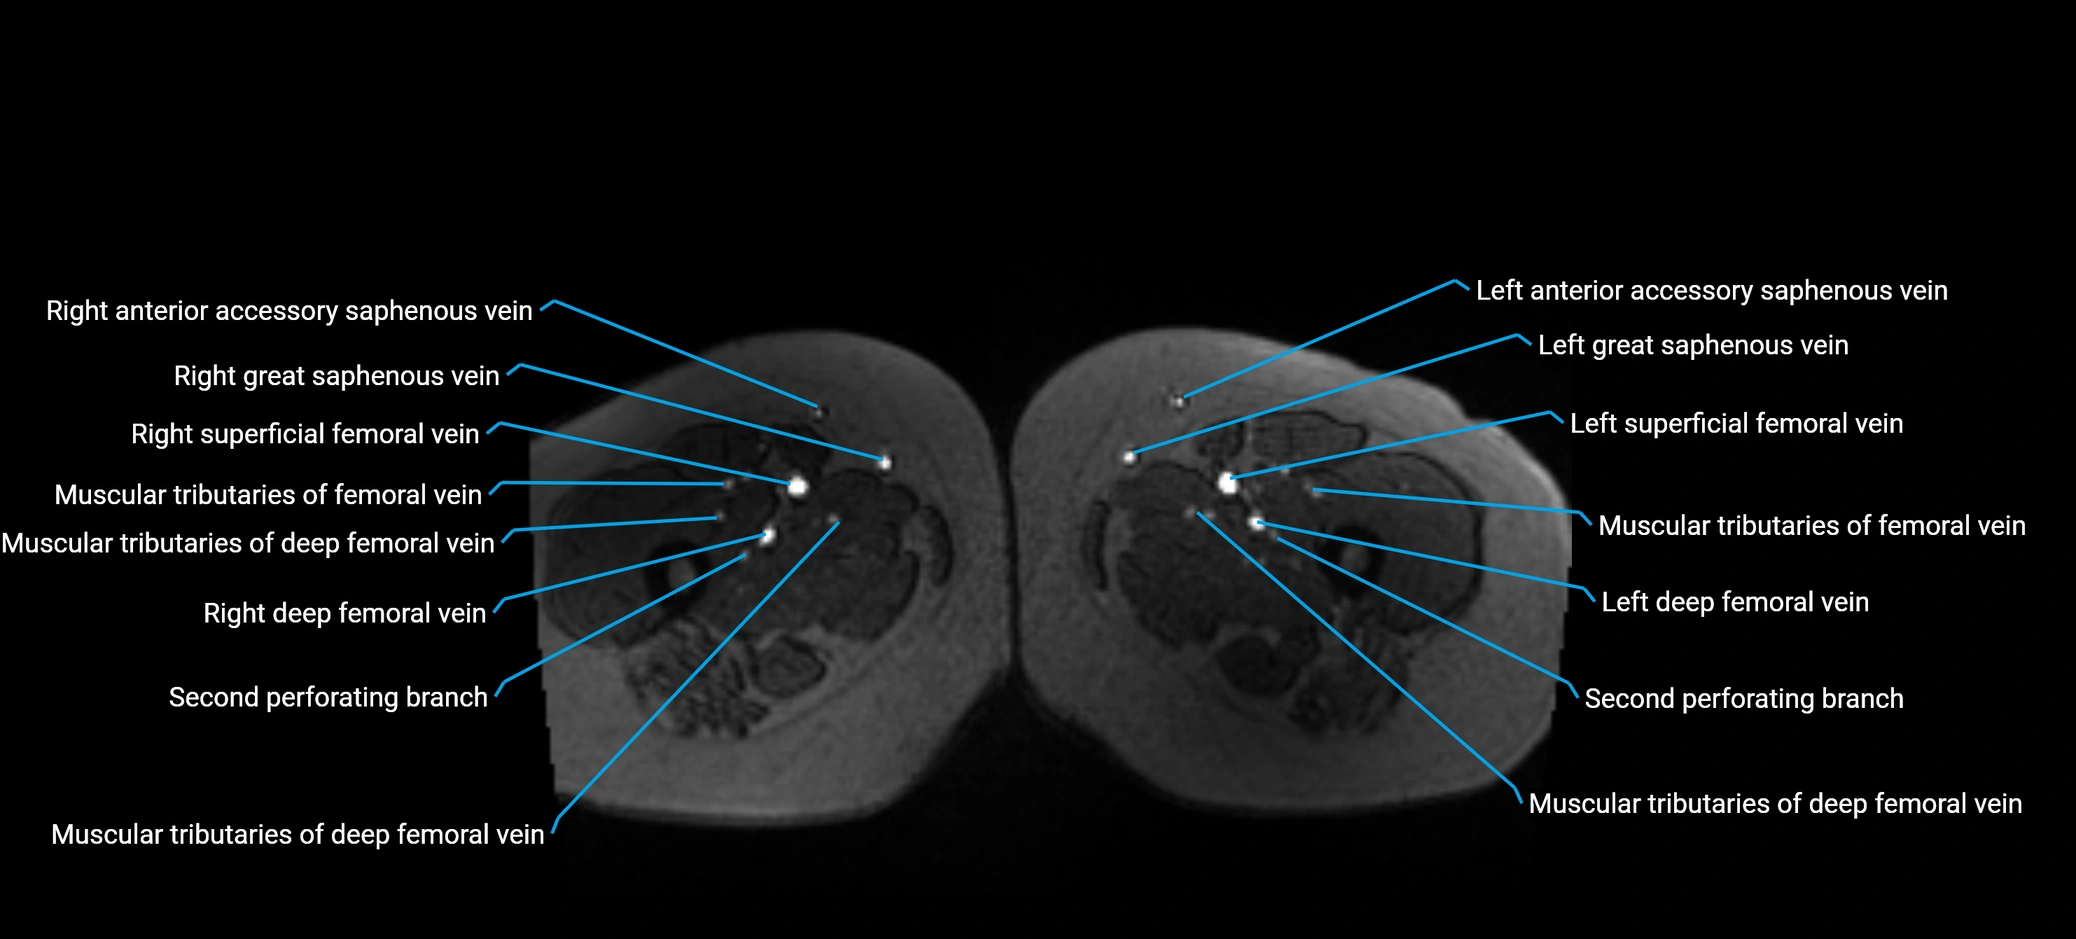

MRI image

image